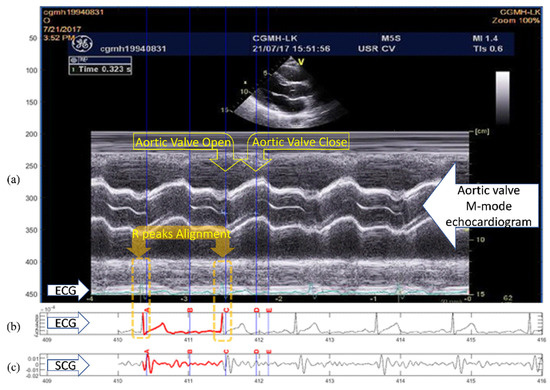

To avoid the waveform distortion during the signal alignment, a reference signal pair of ECG and SCG were screened out from the SCG measurements which had the heart cycle period closest to that of the ECG signal in the echocardiogram image. In Figure 5, a reference signal pair example is illustrated, both the selected RR intervals of the ECG signals in echocardiogram (Figure 5a) and the RR intervals in the reference signal pair (Figure 5b) are the same (966 milliseconds). As the RR interval of the reference ECG signal performing end-to-end alignment with the echocardiogram ECG, no rescaling manipulation was needed. In addition, the entire ECG and SCG signals were considered synchronous to the selected cycle in the echocardiogram on the premise of spontaneous alignment discussed in Figure 4. The aortic valve closing event (annotated by “AC” in Figure 5) identified in the echocardiogram, was mapped to the same temporal place in the reference ECG and SCG signals. The reference SCG signal with fiducial points mapped from the echocardiogram was then used as the intermediary template signal for fiducial point projection to other nonreference measurements. The projection process based on the DTW algorithm, which takes signal morphological similarity into consideration. The revised quasi-synchronous alignment method hereinafter referred to as DTW-based quasi-synchronous alignment.

Figure 5. Illustration of aligning a reference signal pair to the selected echocardiogram section and projecting the specific cardiac event (aortic valve closing, AC) from echocardiogram to SCG curve as the detected fiducial point: (a) Echocardiogram image and the selected section enclosed within vertical lines marked with R1 and R2; (b) The aligned ECG of the reference signal pair; (c) The aligned SCG of the reference signal pair.